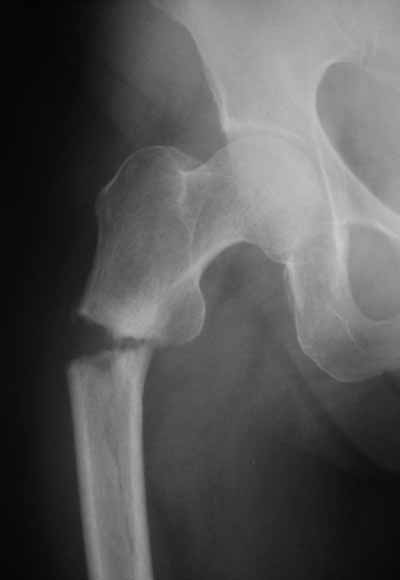

> Я имею ввиду довольно редкий простой поперечный перелом на 1-2 см

> ниже малого вертела.

Тут шеечный винт не фиксировал бы периферический отломок, так что конечно, дистальный винт был бы нужен. Хотя для такого перелома вообще короткий штифт какой-то неуютный выбор.

> > Я имею ввиду довольно редкий простой поперечный перелом на 1-2 см

> > ниже малого вертела.

>

> Тут шеечный винт Не фиксировал бы периферический отломок, так что

> конечно, дистальный винт был бы нужен. Хотя для такого перелома вообще

> короткий штифт какой-то неуютный выбор.

Не думаю так. см вложение.